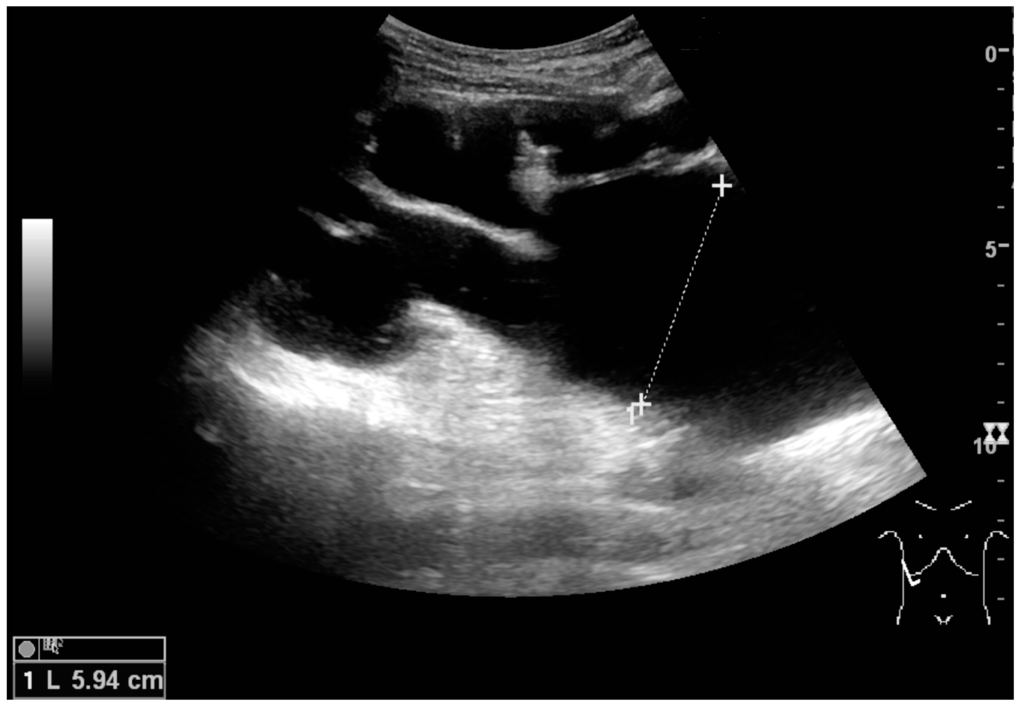

Figure 15. End-stage hydronephrosis with cortical thinning. Measurement of pelvic dilatation on the US image is illustrated by ‘+’ and a dashed line.